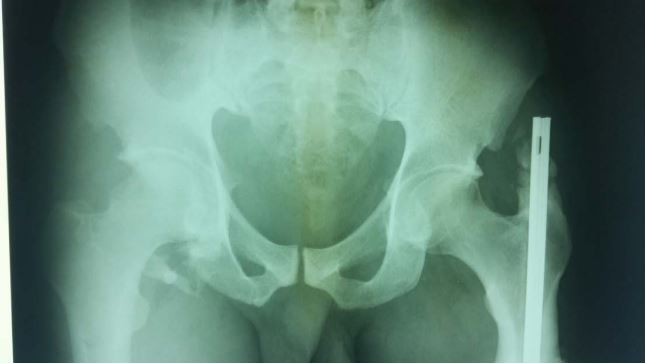

Plain X-rays confirmed a left subtrochanteric fracture and a right obturator dislocation of the hip with an intra-articular incarcerated fragment (Figure 3). Closed reduction of the dislocated hip and surgical treatment of the left subtrochanteric fracture by a Küntscher intramedullary nail; were performed the same day the patient was admitted. Post-reduction radiographs showed an articular gap widening with a defect in the superior lateral femoral head (Figure 4). A confirmation CT scan demonstrated an intra-articular incarcerated fragment (Figure 5). An arthroscopic extraction was warranted, but due to inadequate hospital equipment and patient financial hardship; the patient did not receive appropriate care. Fifteen months later; Mr. SA presented with a control X-ray showing early signs of coxarthrosis and peri-articular ossifications (Figure 6).

Figure 4: Anteroposterior X-ray of the pelvis showing an articular gap widening with a defect in the superior lateral femoral head (patient 3).

Figure 6: Anteroposterior X-ray showing coxarthrosis and peri-articular ossifications (patient3).